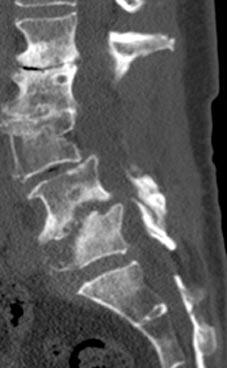

20 year old with severe low back pain from untreated idiopathic adolescent scholiosis who failed all conservative treatment with documented progression of scoliosis despite being done growing.